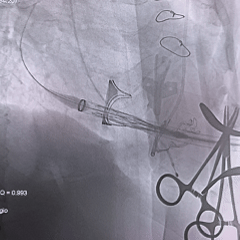

术中影像

右侧垫肩,基本打平原外科瓣瓣架,工作体位:RAO29° CRA12°

瓣膜回收后,旋转输送器弯型调整同轴

瓣膜重新释放至全展开位,可见位置合适,流出端可见形态压缩

28mm球囊后扩,瓣膜形态明显改善

最终评估可见瓣膜形态、位置均理想